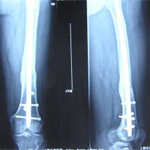

張某,男,50歲,因“左股骨骨不連”入院。植骨+PRP治療后8月完全愈合。

術前